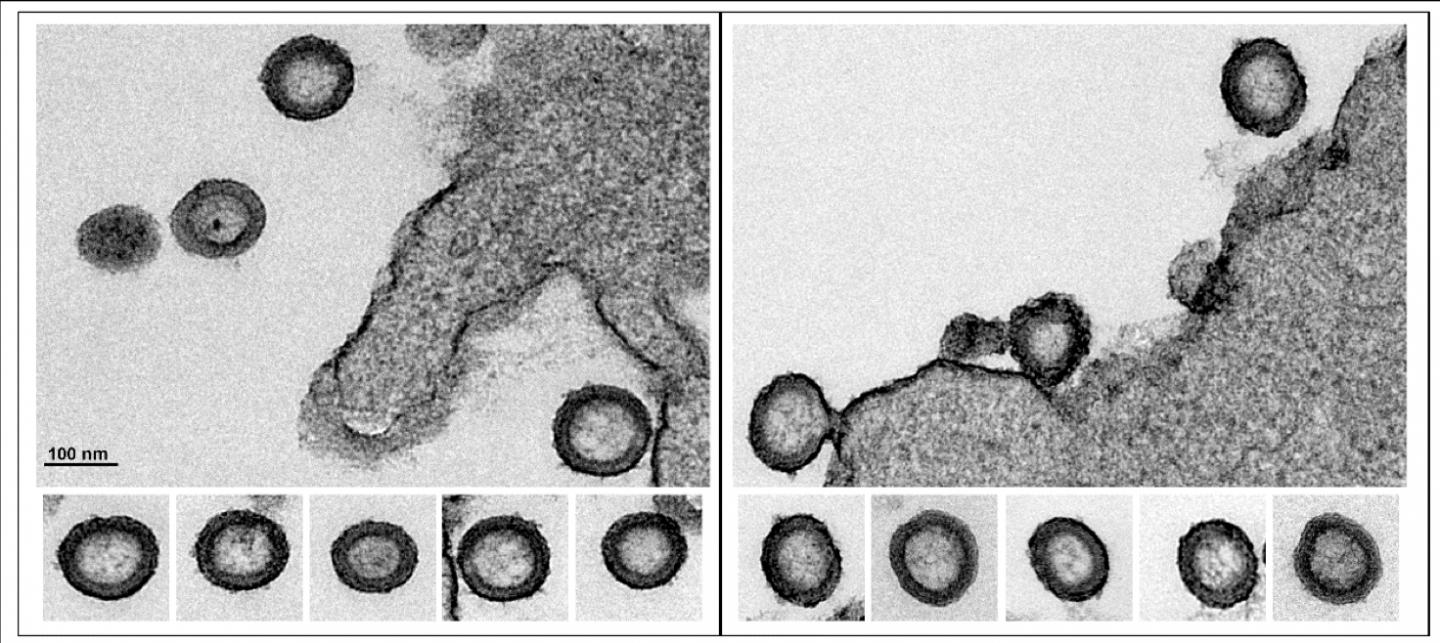

Now, physicists from the University of Utah have pioneered a way of imaging virus-like particles in real time, at room temperature, with impressive resolution. In a new study, the method reveals that the lattice, which forms the major structural component of the human immunodeficiency virus (HIV), is dynamic. The discovery of a diffusing lattice made from Gag and GagPol proteins, long considered to be completely static, opens up potential new therapies.

When HIV particles bud from an infected cell, the viruses experience a lag time before they become infectious. Protease, an enzyme that is embedded as a half-molecule in GagPol proteins, must bond to other similar molecules in a process called dimerization. This triggers the viral maturation that leads to infectious particles. No one knows how these half protease molecules find each other and dimerize, but it may have to do with the rearrangement of the lattice formed by Gag and GagPol proteins that lay just inside of the viral envelope. Gag is the major structural protein and has been shown to be enough to assemble virus-like particles. Gag molecules form a lattice hexagonal structure that intertwines with itself with miniscule gaps interspersed. The new method showed that the Gag protein lattice is not a static one.

The scientists weren't looking for dynamic structures at first--they just wanted to study the Gag protein lattice. Saha led the two year effort to "hack" microscopy techniques to be able to study virus particles at room temperature to observe their behavior in real life. The scale of the virus is miniscule -- about 120 nanometers in diameter--so Saha used interferometric photoactivated localization microscopy (iPALM).

First, Saha tagged the Gag with a fluorescent protein called Dendra2 and produced virus-like particles of the resulting Gag-Dendra2 proteins. These virus-like particles are the same as HIV particles, but made only of the Gag-Dendra2 protein lattice structure. Saha showed that the resulting Gag-Dendra2 proteins assembled the virus-like particles the same way as virus-like particle made up regular Gag proteins. The fluorescent attachment allowed iPALM to image the particle with a 10 nanometer resolution. The scientists found that each immobilized virus-like particle incorporated 1400 to 2400 Gag-Dendra2 proteins arranged in a hexagonal lattice. When they used the iPALM data to reconstruct a time-lapse image of the lattice, it appeared that the lattice of Gag-Dendra2 were not static over time. To make sure, they independently verified it in two ways: mathematically and biochemically.